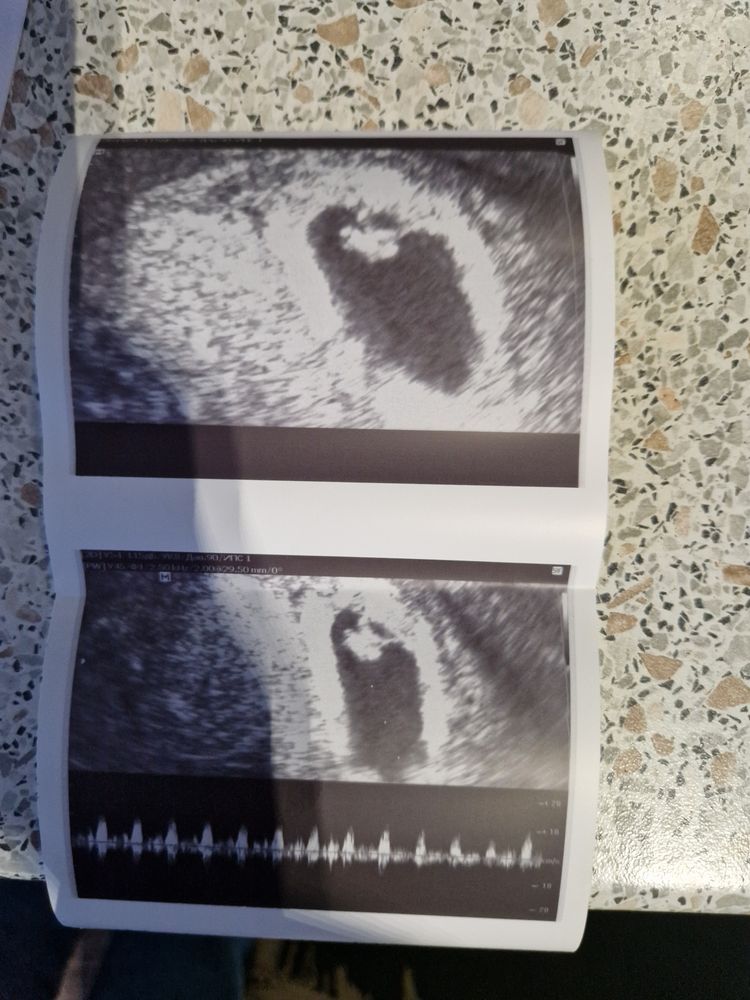

Узи 6н 3 д( 2 желточных мешочка)

Добрый день. У меня так же было. Примерно в 7 недель обнаружили эмбрион и два жм. В 9 недель уже было два эмбриона.В результате родились близнецы. Два жм в одном полном яйце это монохориальная двойня. Яйцеклетка поделилась. Проверьте чуть позже, скорее всего появится второй эмбрион. Удачи Вам 💐.

Елена, да, второй, как-правило, на несколько дней отстает. И желточный мешочек второй поменьше пока. Через неделю повторите узи) ну если не появится, то это называется закладка двойней. Просто один не стал развиваться